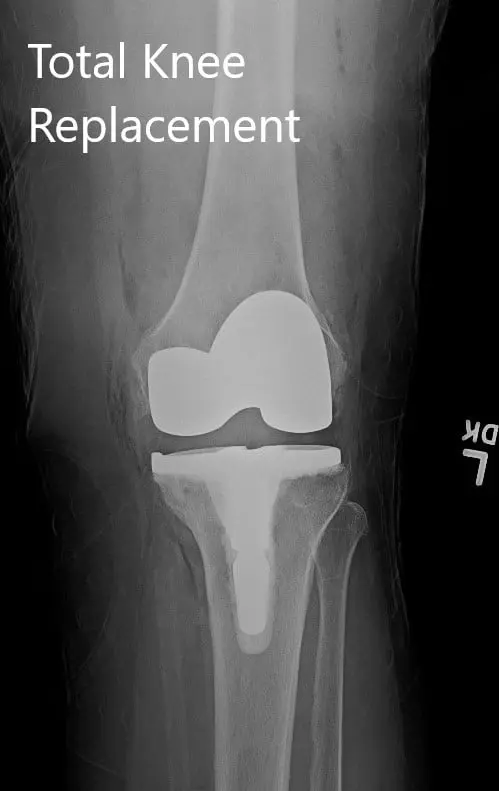

Postoperative X-ray showing the left knee joint with prosthesis in anteroposterior and lateral views

The patient had a good recovery post-op with stable vitals. He was able to walk with support the same day of the surgery. His calves were soft and non-tender with Homan sign negative. The pain was well controlled with medications.

Twelve weeks post-op, he was walking without any support totally pain-free. He had a full range of motion and continued a home exercise program. He was back at his job and expressed satisfaction with the outcome. He reported decreased pain in the right knee secondary to offloading.